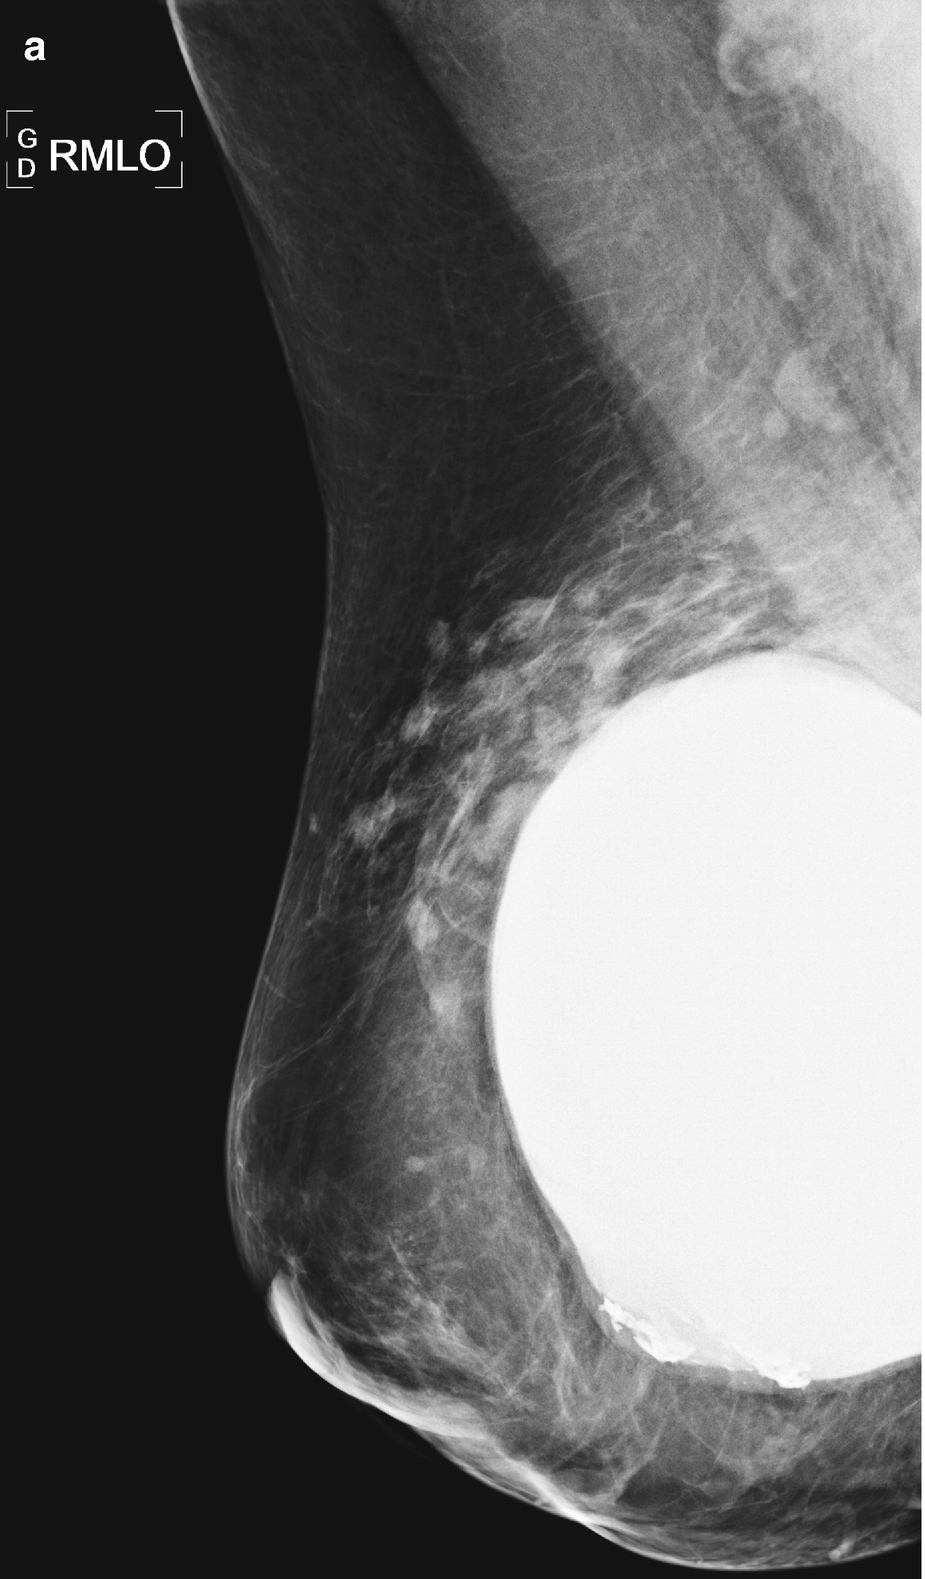

Silicone granuloma (siliconoma) associated with a breast implant. (a) Mammography: siliconomas adjacent to a breast implant. By mammography, it is impossible to determine whether they correspond to an extracapsular rupture or to residual siliconomas secondary to prosthesis replacement. (b) Ultrasound: nodular siliconomas that are echogenic, accompanied by the classic “snowstorm” sign. In this case, ultrasonography demonstrates how the siliconomas are, in fact, residual siliconomas after prosthesis replacement. Note the anechoic structure of the new implant, which determines its integrity

Mammography showing craniocaudal views of both breasts in a patient with prior silicone injections. Note the multiple high-density nodules of different sizes, with circumscribed borders. Some have calcified contours. Generically, nodules produced by the injection of some substances are called siliconomas. Note also the diffuse subdermal compromise caused by infiltration with silicone gel